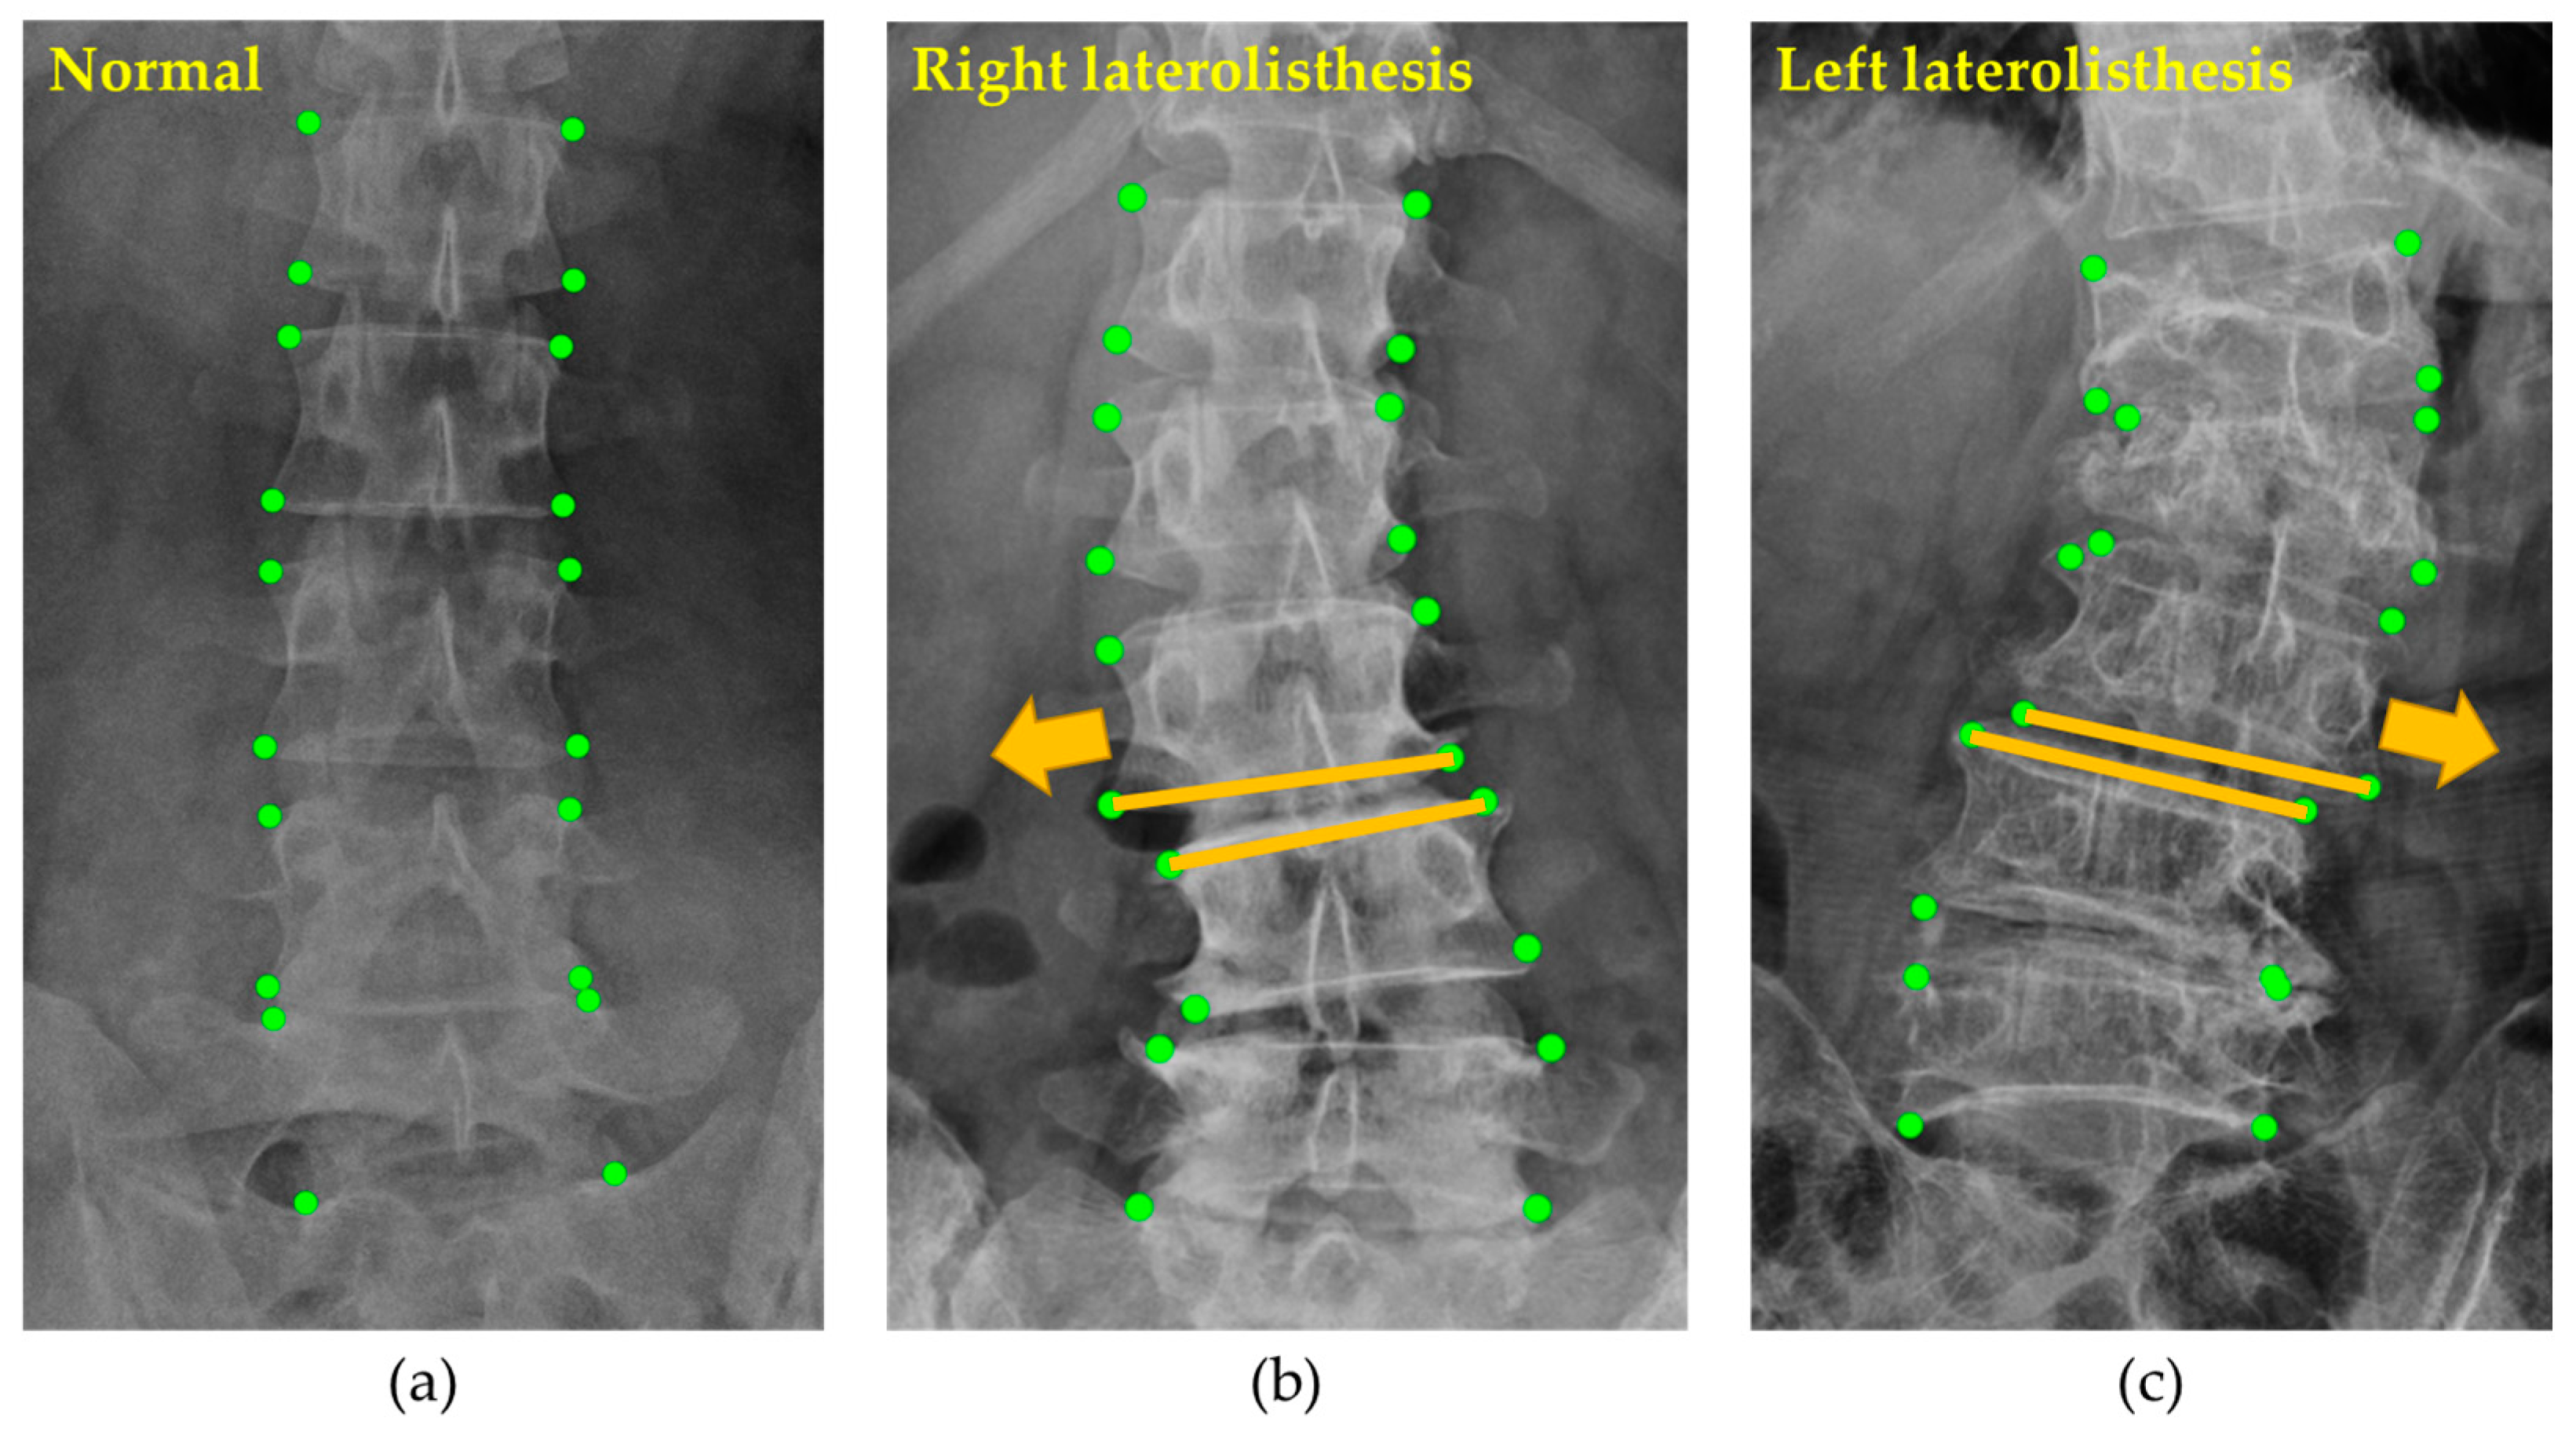

2.2.2. Spondylolisthesis

3.2. Vertebral Corner Point Extraction

3.3. Spondylolisthesis Prediction